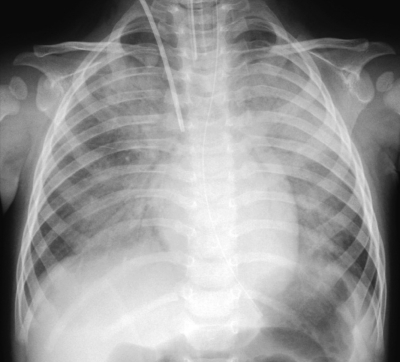

血液所見:赤血球 403 万、Hb 10.4 g/dL、Ht 31 %、白血球 2,300 (好中球 64 %、好酸球 1 %、好塩基球 1 %、単球 7 %、リンパ球 27 %)、血小板 37 万。血液生化学所見:総蛋白 6.1 g/dL、IgG 152 mg/dL(基準 440〜880)、IgA 5 mg/dL(基準 31〜77)、IgM 13 mg/dL(基準 19〜55)。免疫血清学所見:CRP 0.1 mg/dL、β-D-グルカン 26 pg/mL(基準 10 以下)。人工呼吸管理を開始し、胃管と中心静脈カテーテルを挿入した。胸部エックス線写真と肺野条件の胸部 CTとを別に示す。